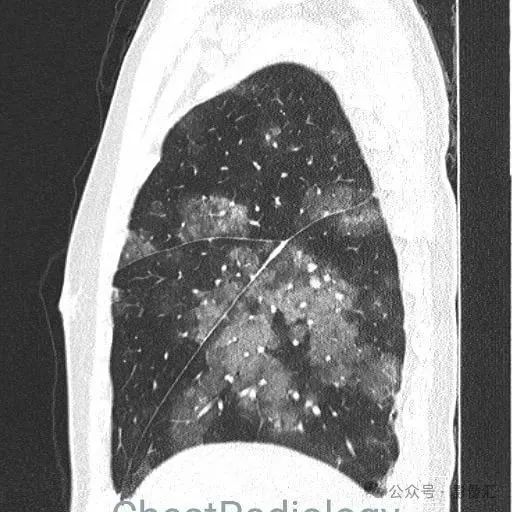

咯血患者,肺部弥漫磨玻璃,细节决定成败?

成年男性,咯血,细节决定成败,你看到了吗?欢迎评论区留言